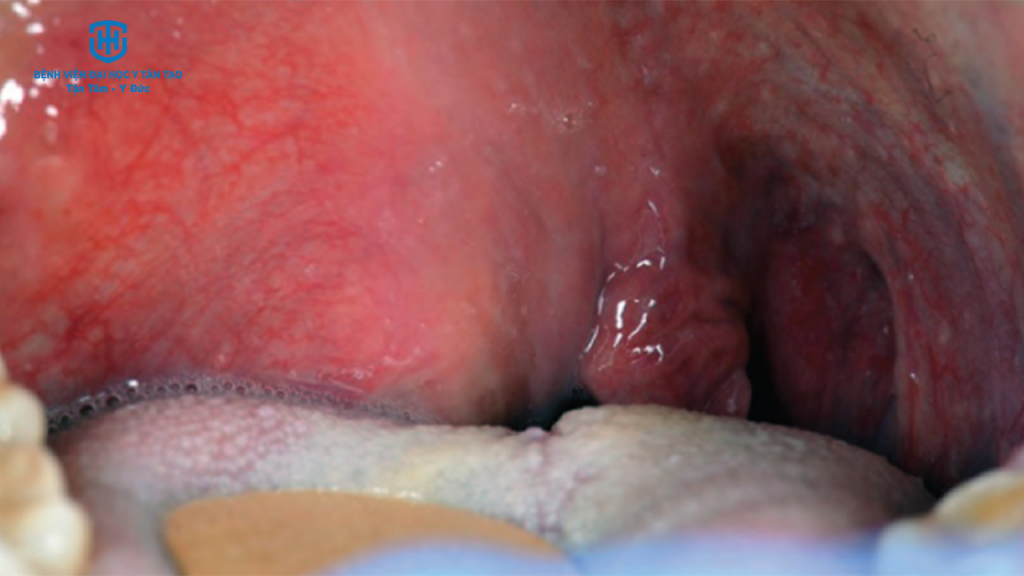

Viêm họng do liên cầu khuẩn là một bệnh nhiễm trùng cấp tính ở miệng họng và amidan. Đây là một bệnh nhiễm trùng rất dễ lây lan do một loại vi khuẩn gọi là Streptococcus nhóm A (strep nhóm A). Khi điều trị thường cần đến thuốc kháng sinh. Những người bị viêm họng do liên cầu khuẩn có khả năng truyền bệnh cho người khác. Trong vài trường hợp, người sau khi bị nhiễm bệnh nhưng không có triệu chứng vẫn có thể lây nhiễm sang người khác.

Nếu không được điều trị kịp thời, viêm họng liên cầu khuẩn có thể gây ra các biến chứng nghiêm trọng như:

- Áp xe quanh amidan.